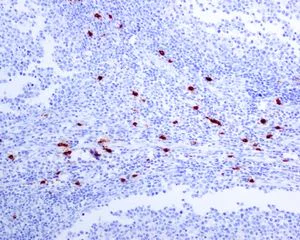

Immunohistochemistry (Formalin/PFA-fixed paraffin-embedded sections) - Anti-Mast Cell Tryptase antibody [EPR8476] - BSA and Azide free (AB227572)

This IHC data was generated using the same anti-Mast Cell Tryptase antibody clone, EPR8476, in a different buffer formulation (cat# ab134932).

Immunohistochemical analysis of paraffin-embedded, formalin-fixed Human colon tissue, labelling Mast Cell Tryptase using ab134932 at a 1/500 dilution.

Heat mediated antigen retrieval was performed with citrate buffer pH 6 before commencing with IHC staining protocol.